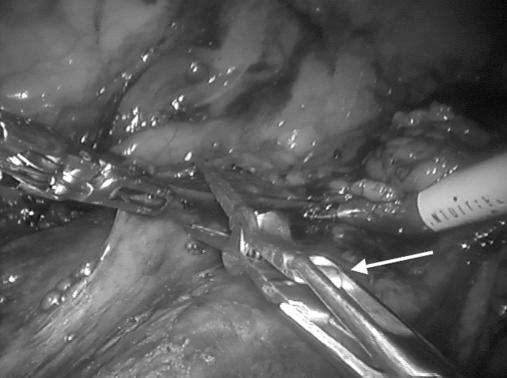

The need for a skilled assistant to perform hilar clamping during robotic partial nephrectomy is a potential limitation of the technique. We describe our experience using robotic bulldog clamps applied by the console surgeon for hilar clamping.

A total of 60 consecutive patients underwent robotic partial nephrectomy, 30 using laparoscopic bulldog clamps applied by the assistant and 30 using robotic bulldog clamps applied with the robotic Prograsp instrument. Perioperative outcomes were compared between groups.

All 30 patients underwent successful hilar clamping during robotic partial nephrectomy using robotic bulldog clamps with no intraoperative complications and without the need for readjustment/reclamping. Robotic bulldog clamps provided adequate ischemia even for tumors >4 cm, hilar, endophytic, multiple tumors, and multiple renal arteries. Both groups had similar baseline characteristics. Perioperative outcomes with robotic bulldog clamps were at least comparable to the laparoscopic bulldog group, with a trend to lower console time, warm ischemia time, and estimated blood loss.

Use of robotically applied bulldog clamps is a safe and feasible method of hilar occlusion during robotic partial nephrectomy; they perform at least as well as laparoscopic bulldog clamps while allowing the console surgeon greater autonomy and precision for hilar clamping.